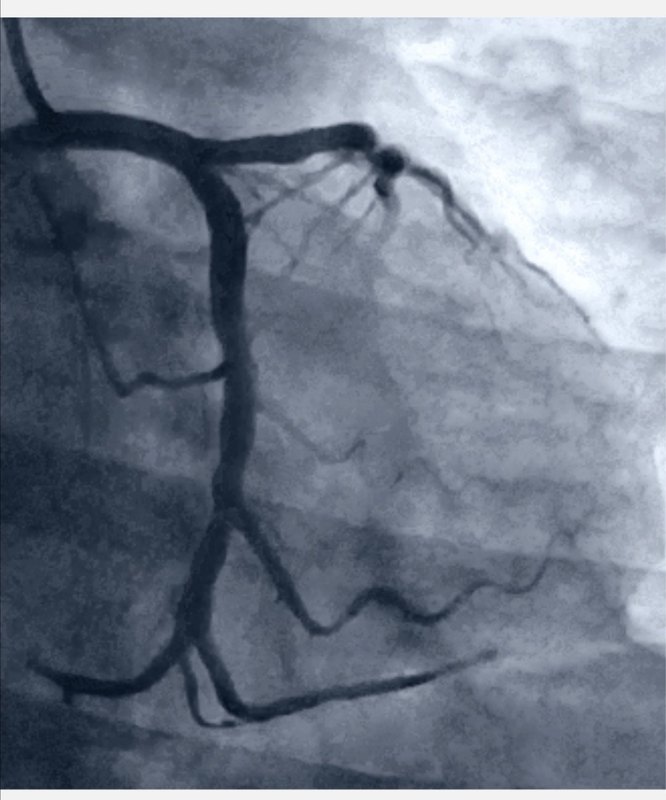

有一位史性患者,來(lái)醫(yī)院時(shí)已經(jīng)有黑蒙暈厥的癥狀了,兒女把她送到醫(yī)院。史大姐的癥狀是頭發(fā)暈,她自己說(shuō)有時(shí)候會(huì)迷糊的感覺(jué)天旋地轉(zhuǎn),左胸左背有時(shí)候疼,除了這些身上沒(méi)有哪兒不舒服了。結(jié)合其他檢查結(jié)果,史大姐的癥狀來(lái)自心臟,造影發(fā)現(xiàn),史大姐冠脈沒(méi)有明顯狹窄,但是心臟主血管前降支前向血流存在非常明顯的慢血流。 這說(shuō)明一個(gè)問(wèn)題:心血管沒(méi)有明顯狹窄也有可能會(huì)出現(xiàn)嚴(yán)重結(jié)果!從史大姐的情況來(lái)看,狹窄0%,但是血流緩慢,已經(jīng)導(dǎo)致了她出現(xiàn)暈厥黑蒙的癥狀,是非常危險(xiǎn)緊急的。心血管疾病中除了狹窄,還有一個(gè)微血管狹窄,也就是慢血流,也要重視。

許多患者都問(wèn)過(guò),血管狹窄75%在放支架行不行?狹窄70%不放風(fēng)險(xiǎn)大不大?放支架究竟有沒(méi)有什么標(biāo)準(zhǔn)?我們今天來(lái)給大家科普一下這個(gè)問(wèn)題。首先要說(shuō),血管狹窄是判斷是否要放支架的一個(gè)標(biāo)準(zhǔn)。但是!不是唯一標(biāo)準(zhǔn)。第一,血管要有病變,不論何種性質(zhì)的、何種程度,血管首先要有病變;第二,這個(gè)病變變導(dǎo)致了左心室10%以上的心肌缺血;第三,出現(xiàn)以上兩種情況后,還要用充足的藥物治療,當(dāng)充分的藥物治療不能夠解決這個(gè)缺血,這時(shí)候,我們才會(huì)推薦患者做支架。就像警察抓小偷一樣:一個(gè)人看起來(lái)賊眉鼠眼(就像血管檢查出狹窄了),不能說(shuō)他是小偷,只有當(dāng)他有偷東西的行為后(這個(gè)狹窄的血管導(dǎo)致了心肌缺血),才能說(shuō)他是小偷,警察才會(huì)抓他。這三個(gè)條件(血管病變、導(dǎo)致缺血、藥物無(wú)效)要同時(shí)具備,才會(huì)為患者考慮放支架或其他方法。不同時(shí)具備以上三種條件的,不論血管狹窄到什么程度,都不需要放支架。同時(shí),當(dāng)具備這三種條件時(shí),我們也有三種方案。第一,就是支架術(shù);第二,外科搭橋術(shù);第三則是根據(jù)患者的自身意愿,選擇放棄。